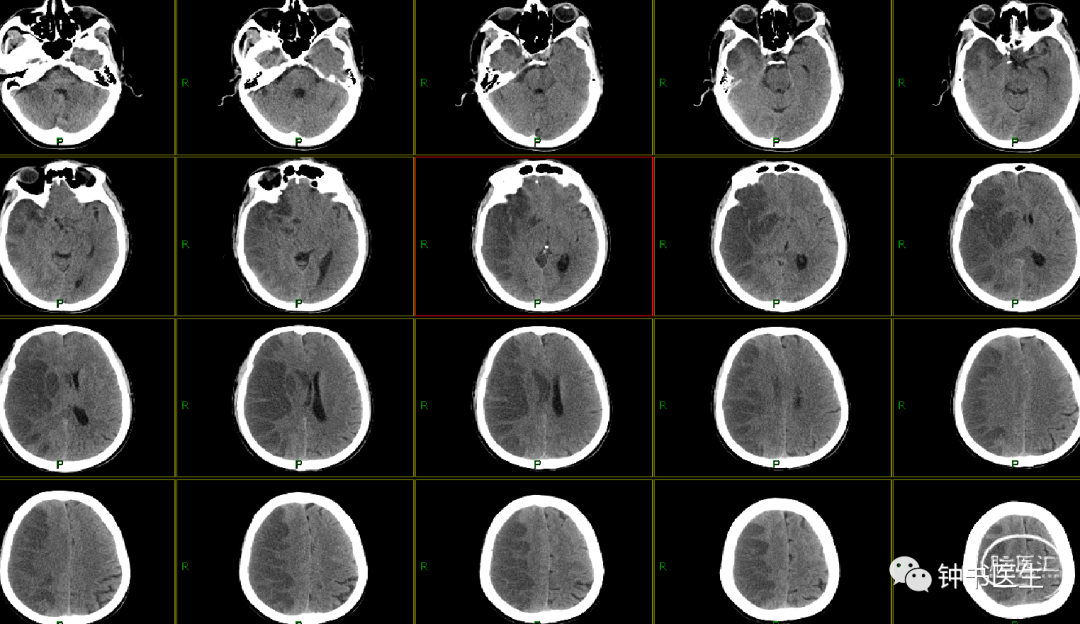

病例1

56y,意识不清伴右侧肢体无力5小时,GCS8分

再灌注损伤(出血):需降压

出血疼痛、烦躁,血压高

镇静镇痛影响神志观察

2012-11-8 CT

左颞部脑梗加重,出血渗出点增多。继续加强镇静镇痛治疗。

2012-11-10 CT

病情趋稳定,转出监护室治疗。

病例2

患者,女,78岁

突发右侧肢体无力5小时入院

高血压病20余年,予培哚普利降压。有糖尿病史4年,予阿卡波糖控制血糖。

BP:188mmHg/89mmHg

神清,语对答切题,右侧鼻唇沟偏浅,右上肢肌力2级,右下肢肢体肌力2级。

2017-7-6 CT

2017-7-7 CT

2017-7-12 CT

病例3

男,64岁

因“突发意识障碍2天” 入院

神志模糊,言语含糊,查体不配合,左侧肢体肌力3级。

Bp:131/66mmHg

2019-1-10 当地CT

2019-1-12 当地CT

2019-1-12

2019-1-13

2019-1-14

2019-1-16

2019-1-19